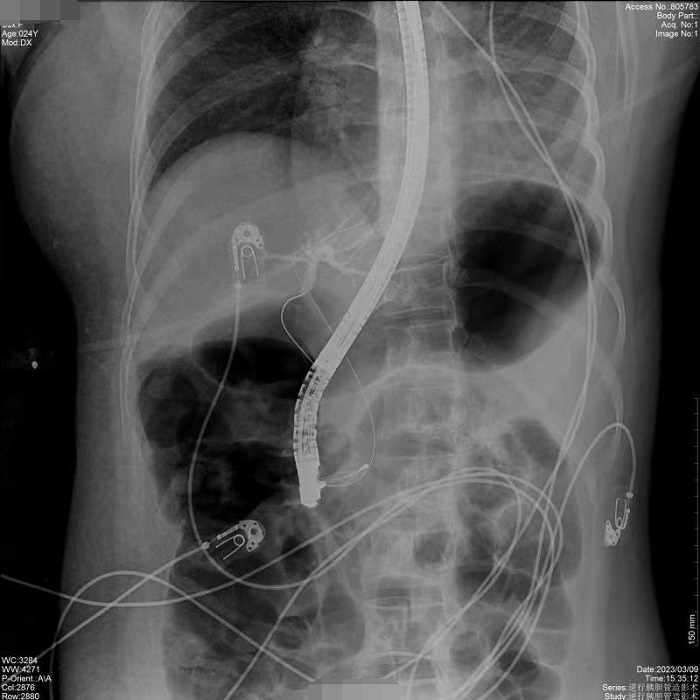

病例1:患者間斷上腹部脹痛4月,經(jīng)磁共振膽道水成像(MRCP)明確為膽總管結(jié)石、膽囊結(jié)石。常規(guī)手術(shù)需要膽總管切開取石,考慮其自身的訴求,醫(yī)生決定嘗試為患者做內(nèi)鏡逆行膽管造影術(shù),幫助實(shí)現(xiàn)最小創(chuàng)傷及快速康復(fù)。術(shù)中,通過十二指腸鏡,將導(dǎo)絲通過十二指腸乳頭(即膽總管的下端開口處)置入膽管內(nèi),在X線透視下注射造影劑造影,完成對膽總管內(nèi)情況診斷,并在診斷基礎(chǔ)之上完成取石治療。